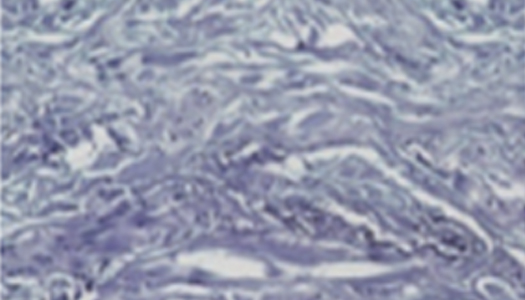

• 콜라겐

3MONTH

• 엘라비에 리투오

6MONTH

• 엘라비에 리투오2.9배 증가

• 엘라비에 리투오3.2배 증가

리투오가 비교 대조군 대비 콜라겐 생성효과가 뛰어남을 확인

*파란색이 콜라겐